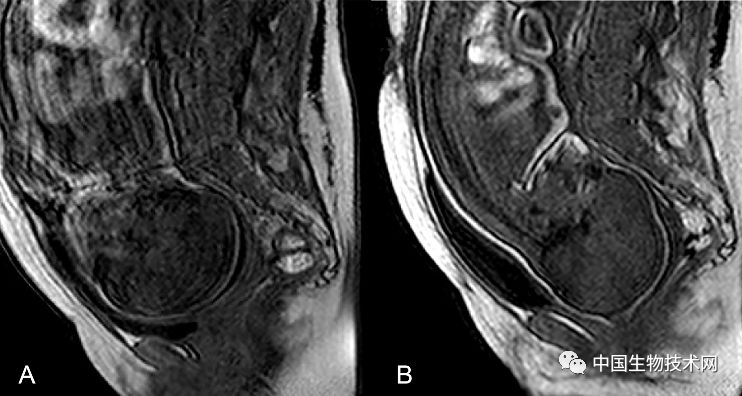

近日,法国克莱蒙奥弗涅大学的研究人员利用三维磁共振成像(MRI)技术,拍摄了显示胎儿大脑和头骨在分娩前通过产道时如何改变形状的三维图像。该研究结果近日已发表在《PLOS ONE》上。

在这项新研究中,为了证明和描述胎头成型和分娩过程中大脑形状的变化,Olivier Ami博士领导的研究团队使用三维MRI捕捉了7名胎儿在分娩前和第二产程中头骨和大脑的详细图像。该分析揭示了所有7名胎儿在第二产程都有胎头成型,其中颅骨的不同部位存在不同程度地重叠。其中5名新生儿的头骨和大脑形状恢复到出生前的状态,但另外2名新生儿的头骨和大脑形状仍在变化。胎头成型程度最高的三名新生儿中有两名是通过紧急剖腹产手术分娩的,另一个是通过阴道分娩的。

总的来说,该研究结果表明,胎儿在出生时承受的颅骨压力比之前所认为的要大,这可能是许多顺产新生儿出现无症状性脑出血和视网膜出血的潜在原因。

Ami补充道:“在阴道分娩的过程中,胎儿的大脑形状会根据颅骨重叠的程度发生不同程度的变形。大多数新生儿出生后颅骨成型不再明显。有些头骨顺应变形以便于分娩,而另一些头骨不容易顺应变形。”